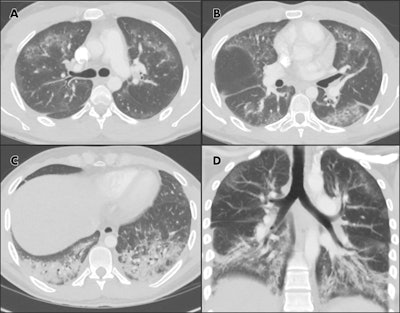

Chest CTA images in 24-year-old man with a history of e-cigarette use. A-C, select axial sections of the lung presented on lung windows reveal patchy ground-glass opacities distributed bilaterally with some, A, B, subpleural sparing and, C, consolidation in the lung bases. D, coronal oblique thick-slab average intensity reconstruction shows the predominance of the findings in the basal lungs and demonstrates the peripheral subpleural sparing. Images courtesy of RSNA.Abbarra and Kay wrote that their patient shared many of the same clinical and radiological features found in the cases reported from Wisconsin and Illinois, such as a combination of acute respiratory symptoms with fever and elevated white blood cell counts. These are suspicious for infection, which is typically excluded on further investigation.

Radiography findings on chest x-ray were nonspecific, consisting of bilateral and basilar predominant opacities; on CT these were confirmed to be a combination of ground-glass opacities and consolidation. Clinicians also observed relative preservation of the subpleural regions of the lungs, another feature reported in the Wisconsin and Illinois cases.

Abbarra and Kay believe that this latter phenomenon could be related to the main involvement of the central aspect of the secondary pulmonary lobule, which is believed to be a response to an inhaled agent.